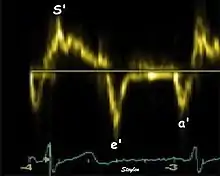

Spectral tissue velocity curves from the mitral annulus at the septal (left) and lateral (right) points. The curves show multiple heartbeats.

Pulsed wave spectral tissue Doppler has become a universal tool that is part of the general echocardiographic examination. Like any other echocardiographic measurement, measures by tissue Doppler should be interpreted in the context of the whole examination. The velocity curves are in general taken from the base of the mitral annulus at the insertion of the mitral leaflets, in the septal and lateral points of the four chamber view, and eventually the anterior and inferior points of the two-chamber views. For the right ventricle it is customary to use the lateral point of the tricuspid annulus only. Averaging peak velocities from the septal and lateral point has become common, although it has been shown that averaging all four points mentioned above, gives significantly less variability[3]

The method measures annular velocities to and from the probe during the heart cycle.

Single spectral tissue velocity curve from the mitral annulus. The curve shows velocities towards the probe (positive velocity) in systole, and away from the probe (negative velocities) in diastole. The most useful measures are the peak velocities, in systole S' and in early diastole (e') and late diastole during atrial contraction (a').

Annular velocities summarize the longitudinal contraction of the ventricle during systole, and elongation during diastole. Peak velocities are commonly used.